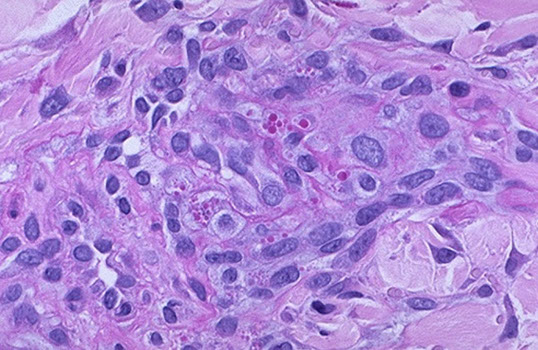

Giant cell arteritis of the breast. The vessel wall has been replaced by granulomatous inflammation. The process has compressed the vessel lumen to near-complete obstruction. A giant cell is shown in this field. B, Giant cell arteritis of the breast. Granulomatous inflammation and fibrinoid necrosis are shown within the wall of this vessel. C, Giant cell arteritis of the breast. The special elastin stain highlights the fragmentation of the internal elastic

lamina in this vessel (hematoxylin-eosin, original magnifications320 [A and B]; original magnification320 [C]).